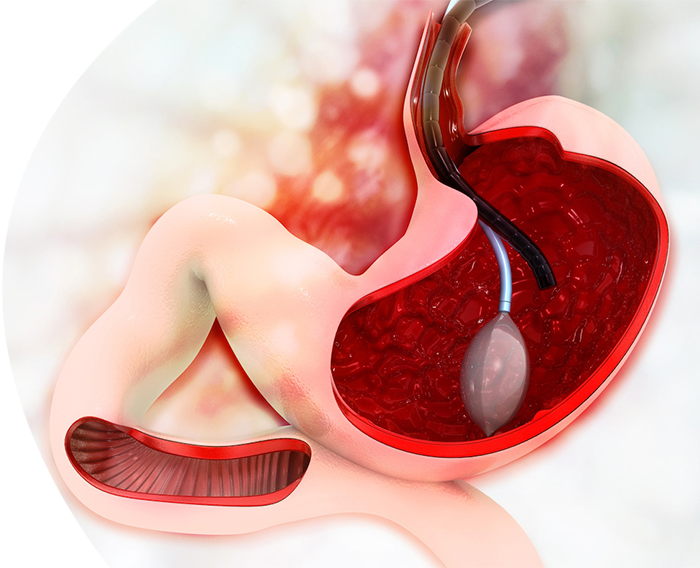

بالون المعدة

بالون المعدة هو إجراء غير جراحي لتخسيس الوزن يتم فيه وضع بالون سيليكون مملوء بمحلول ملحي في المعدة، ليحتل حيزاً فيها ويُحدث شعوراً بالامتلاء والشبع بعد تناول كمية قليلة من الطعام، مما يساعد على فقدان الوزن. يعد هذا الإجراء مؤقتًا، وعادة ما تبقى البالون في المعدة لمدة ستة أشهر، ويتم سحبه بعد انتهاء المدة المحددة. يتميز بأنه حل للمرضى الذين لم تنجح معهم طرق إنقاص الوزن الأخرى، لكنه يتطلب التزامًا بنظام غذائي صحي وممارسة الرياضة لتحقيق أفضل النتائج، ويجب أن يتم تحت إشراف طبي متخصص